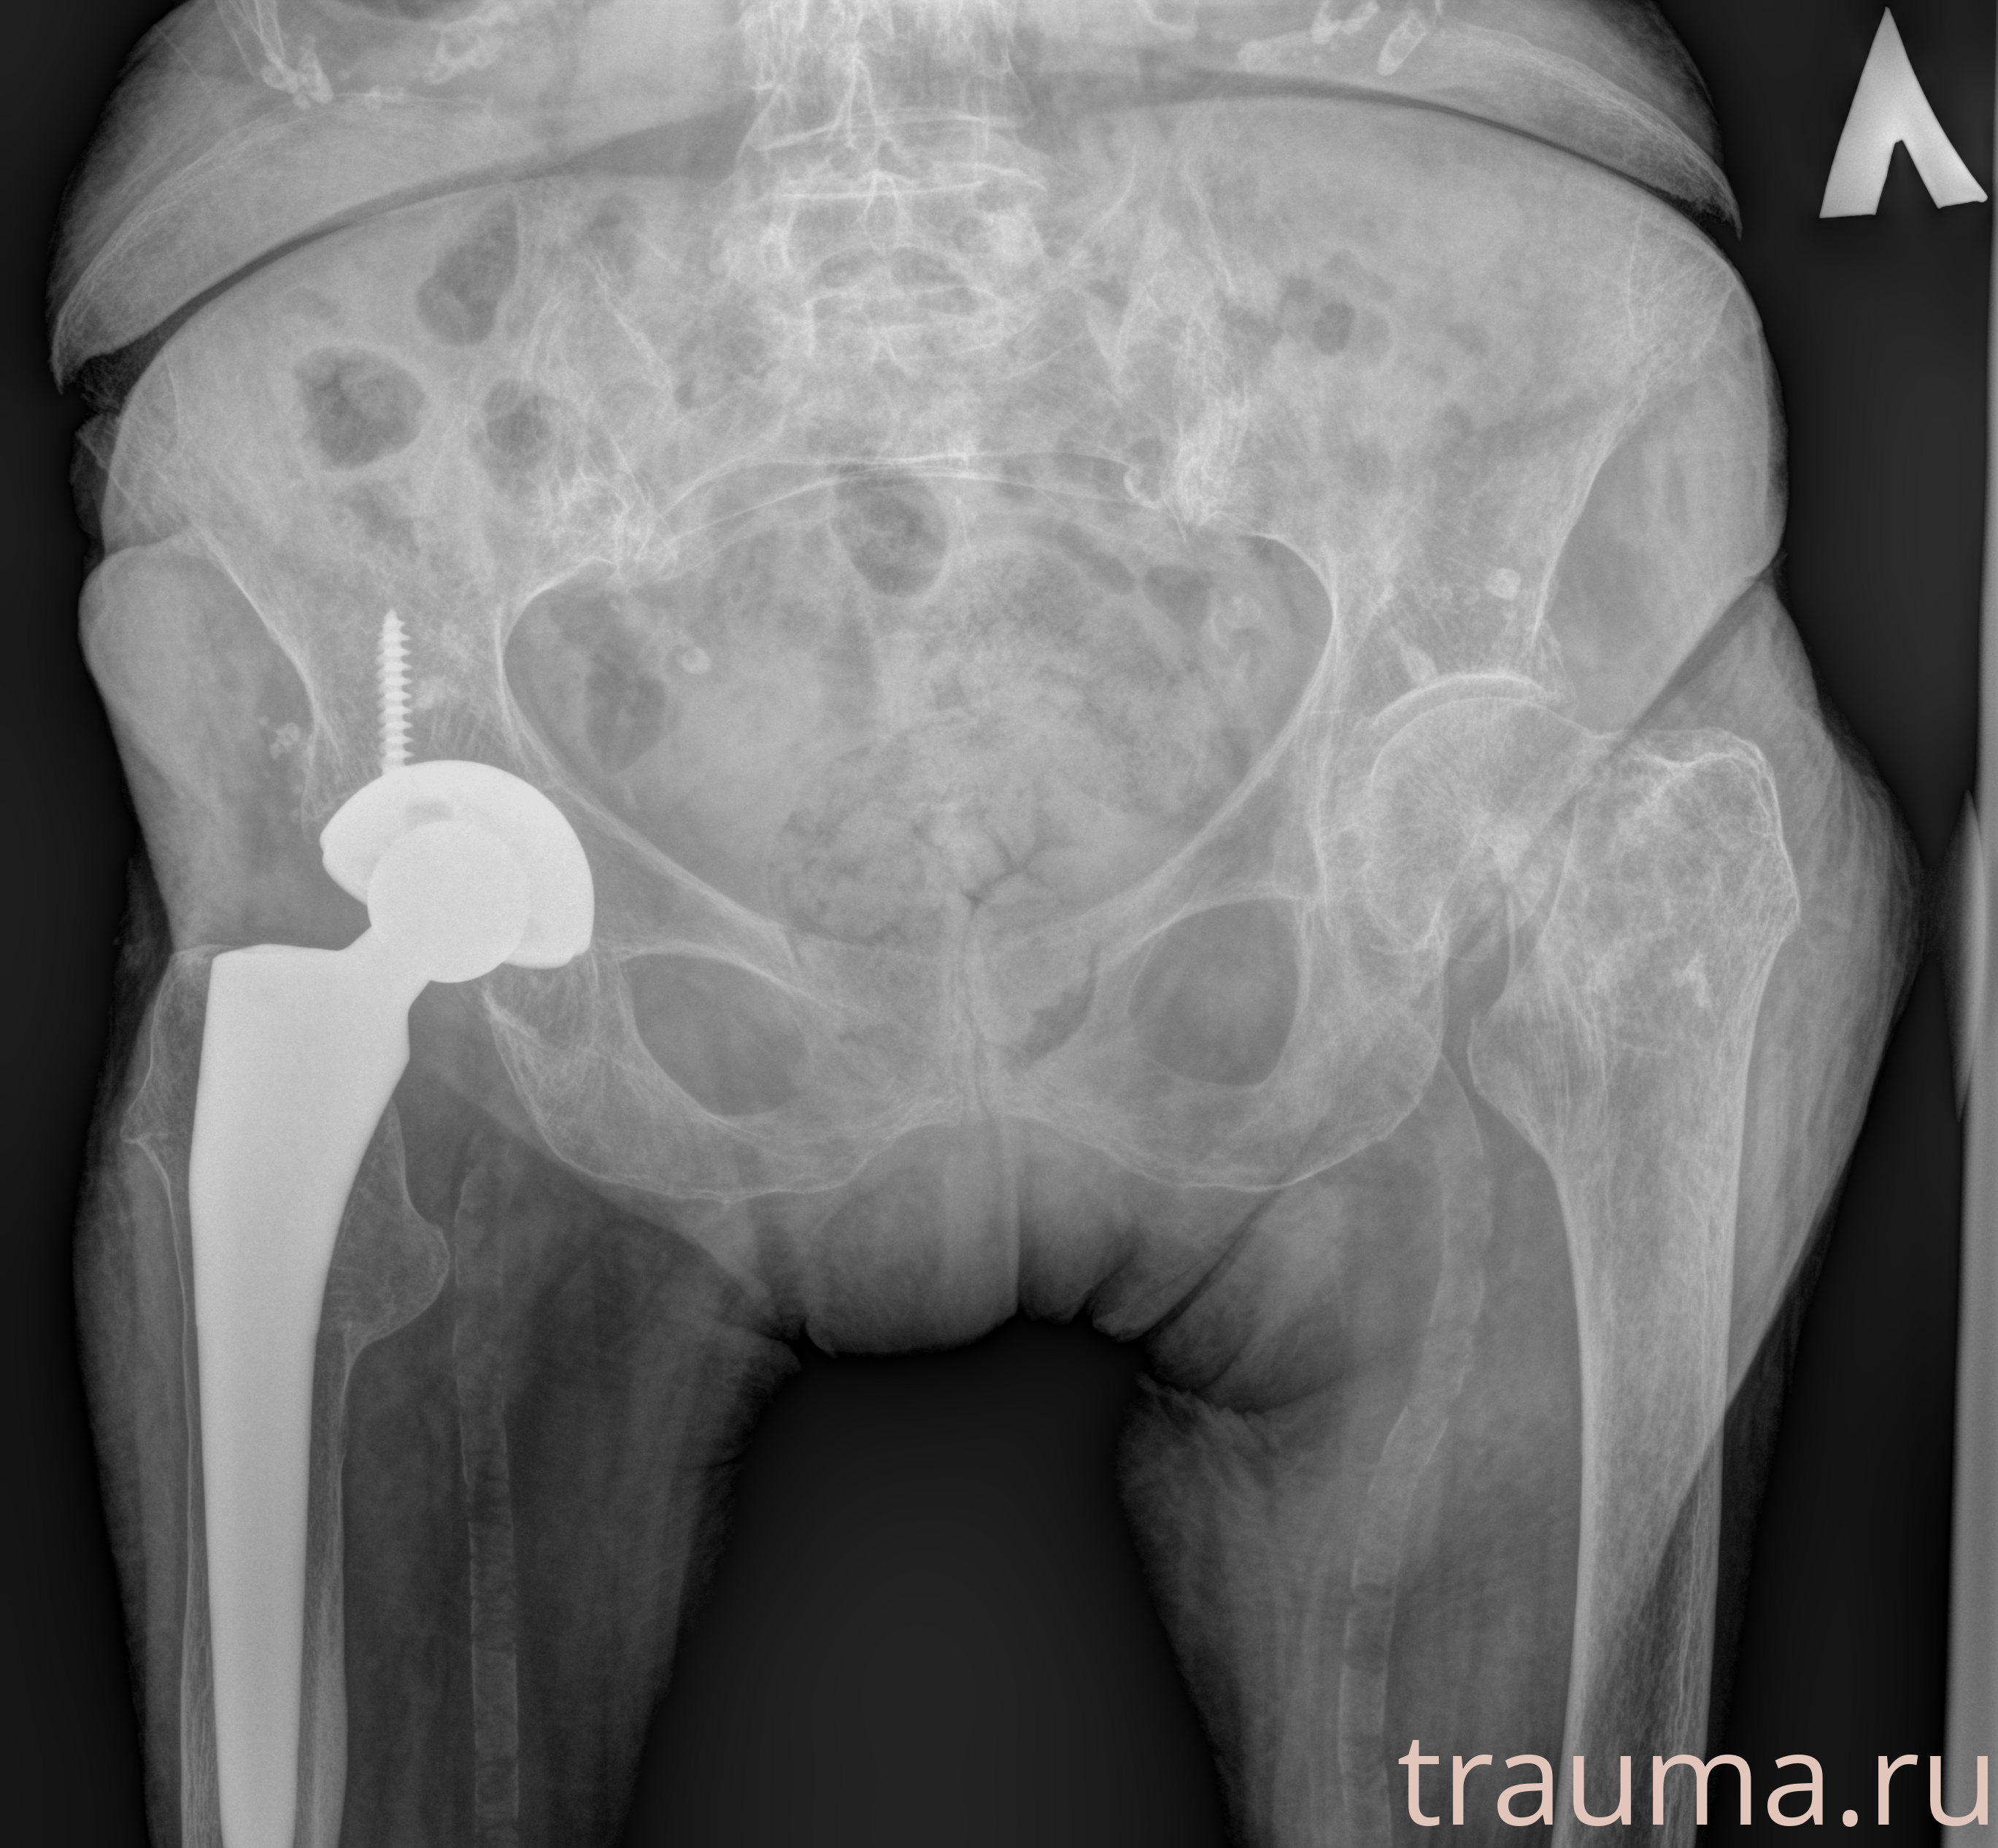

Рентген на дому: по вашему адресу приезжает врач-рентгенолог, травматолог-ортопед с мобильным рентгеновским аппаратом, проводит диагностику травмы или заболевания, делает необходимые рентгенограммы, дает рекомендации по дальнейшему лечению. Получить качественные снимки в домашних условиях возможно благодаря уникальной методике, разработанной МосРентген Центром для института  Склифосовского